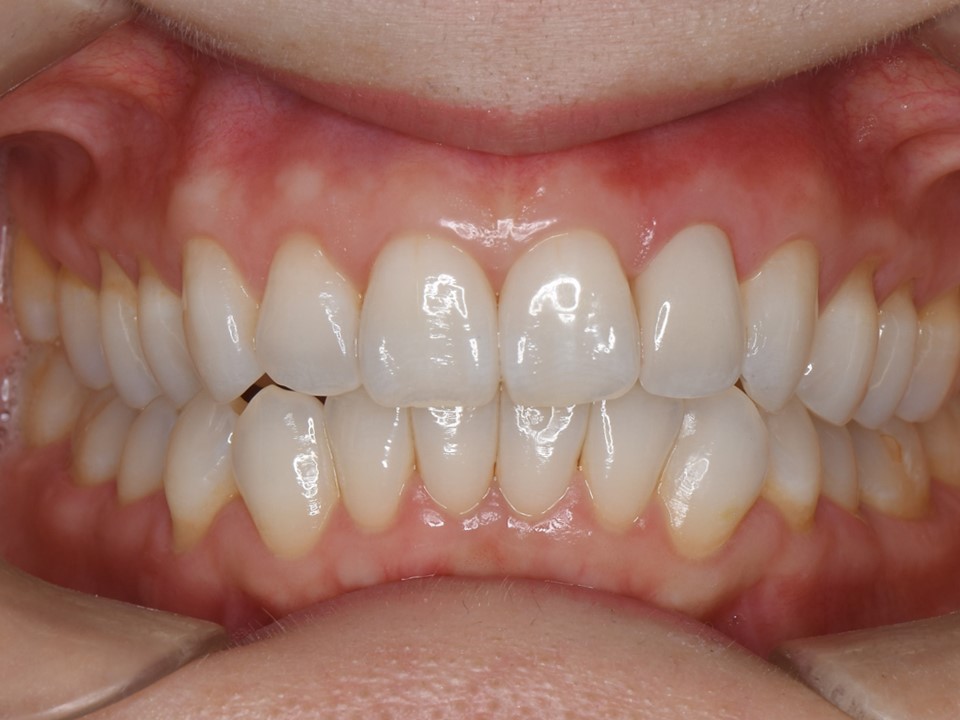

初診時口腔内。左側側切歯(⇒)のブラックマージンを主訴に来院。セラミッククラウンの色も透明感が無く、審美的な改善を希望。

装着してあるセラミッククラウンが不適合のため、歯茎に炎症を認める。